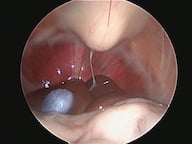

Endoscopia Rígida

A Clínica Veterinária de Albufeira já disponibiliza serviços de minima invasão como solução alternativa às cirurgias tradicionais, sejam estas profiláticas (como as ovariohisterectomias, orquiectomia de criptorquideos) ou de diagnóstico (biópsia, cistotomias, etc). A mais valia desta técnica é a utilização de orifícios naturais ou incisões minímas para aceder ao sistema desejado ( urinário, respiratório, digestivo, reprodutivo), sendo a recuperação mais rápida e a dor pós operatória muito menor.